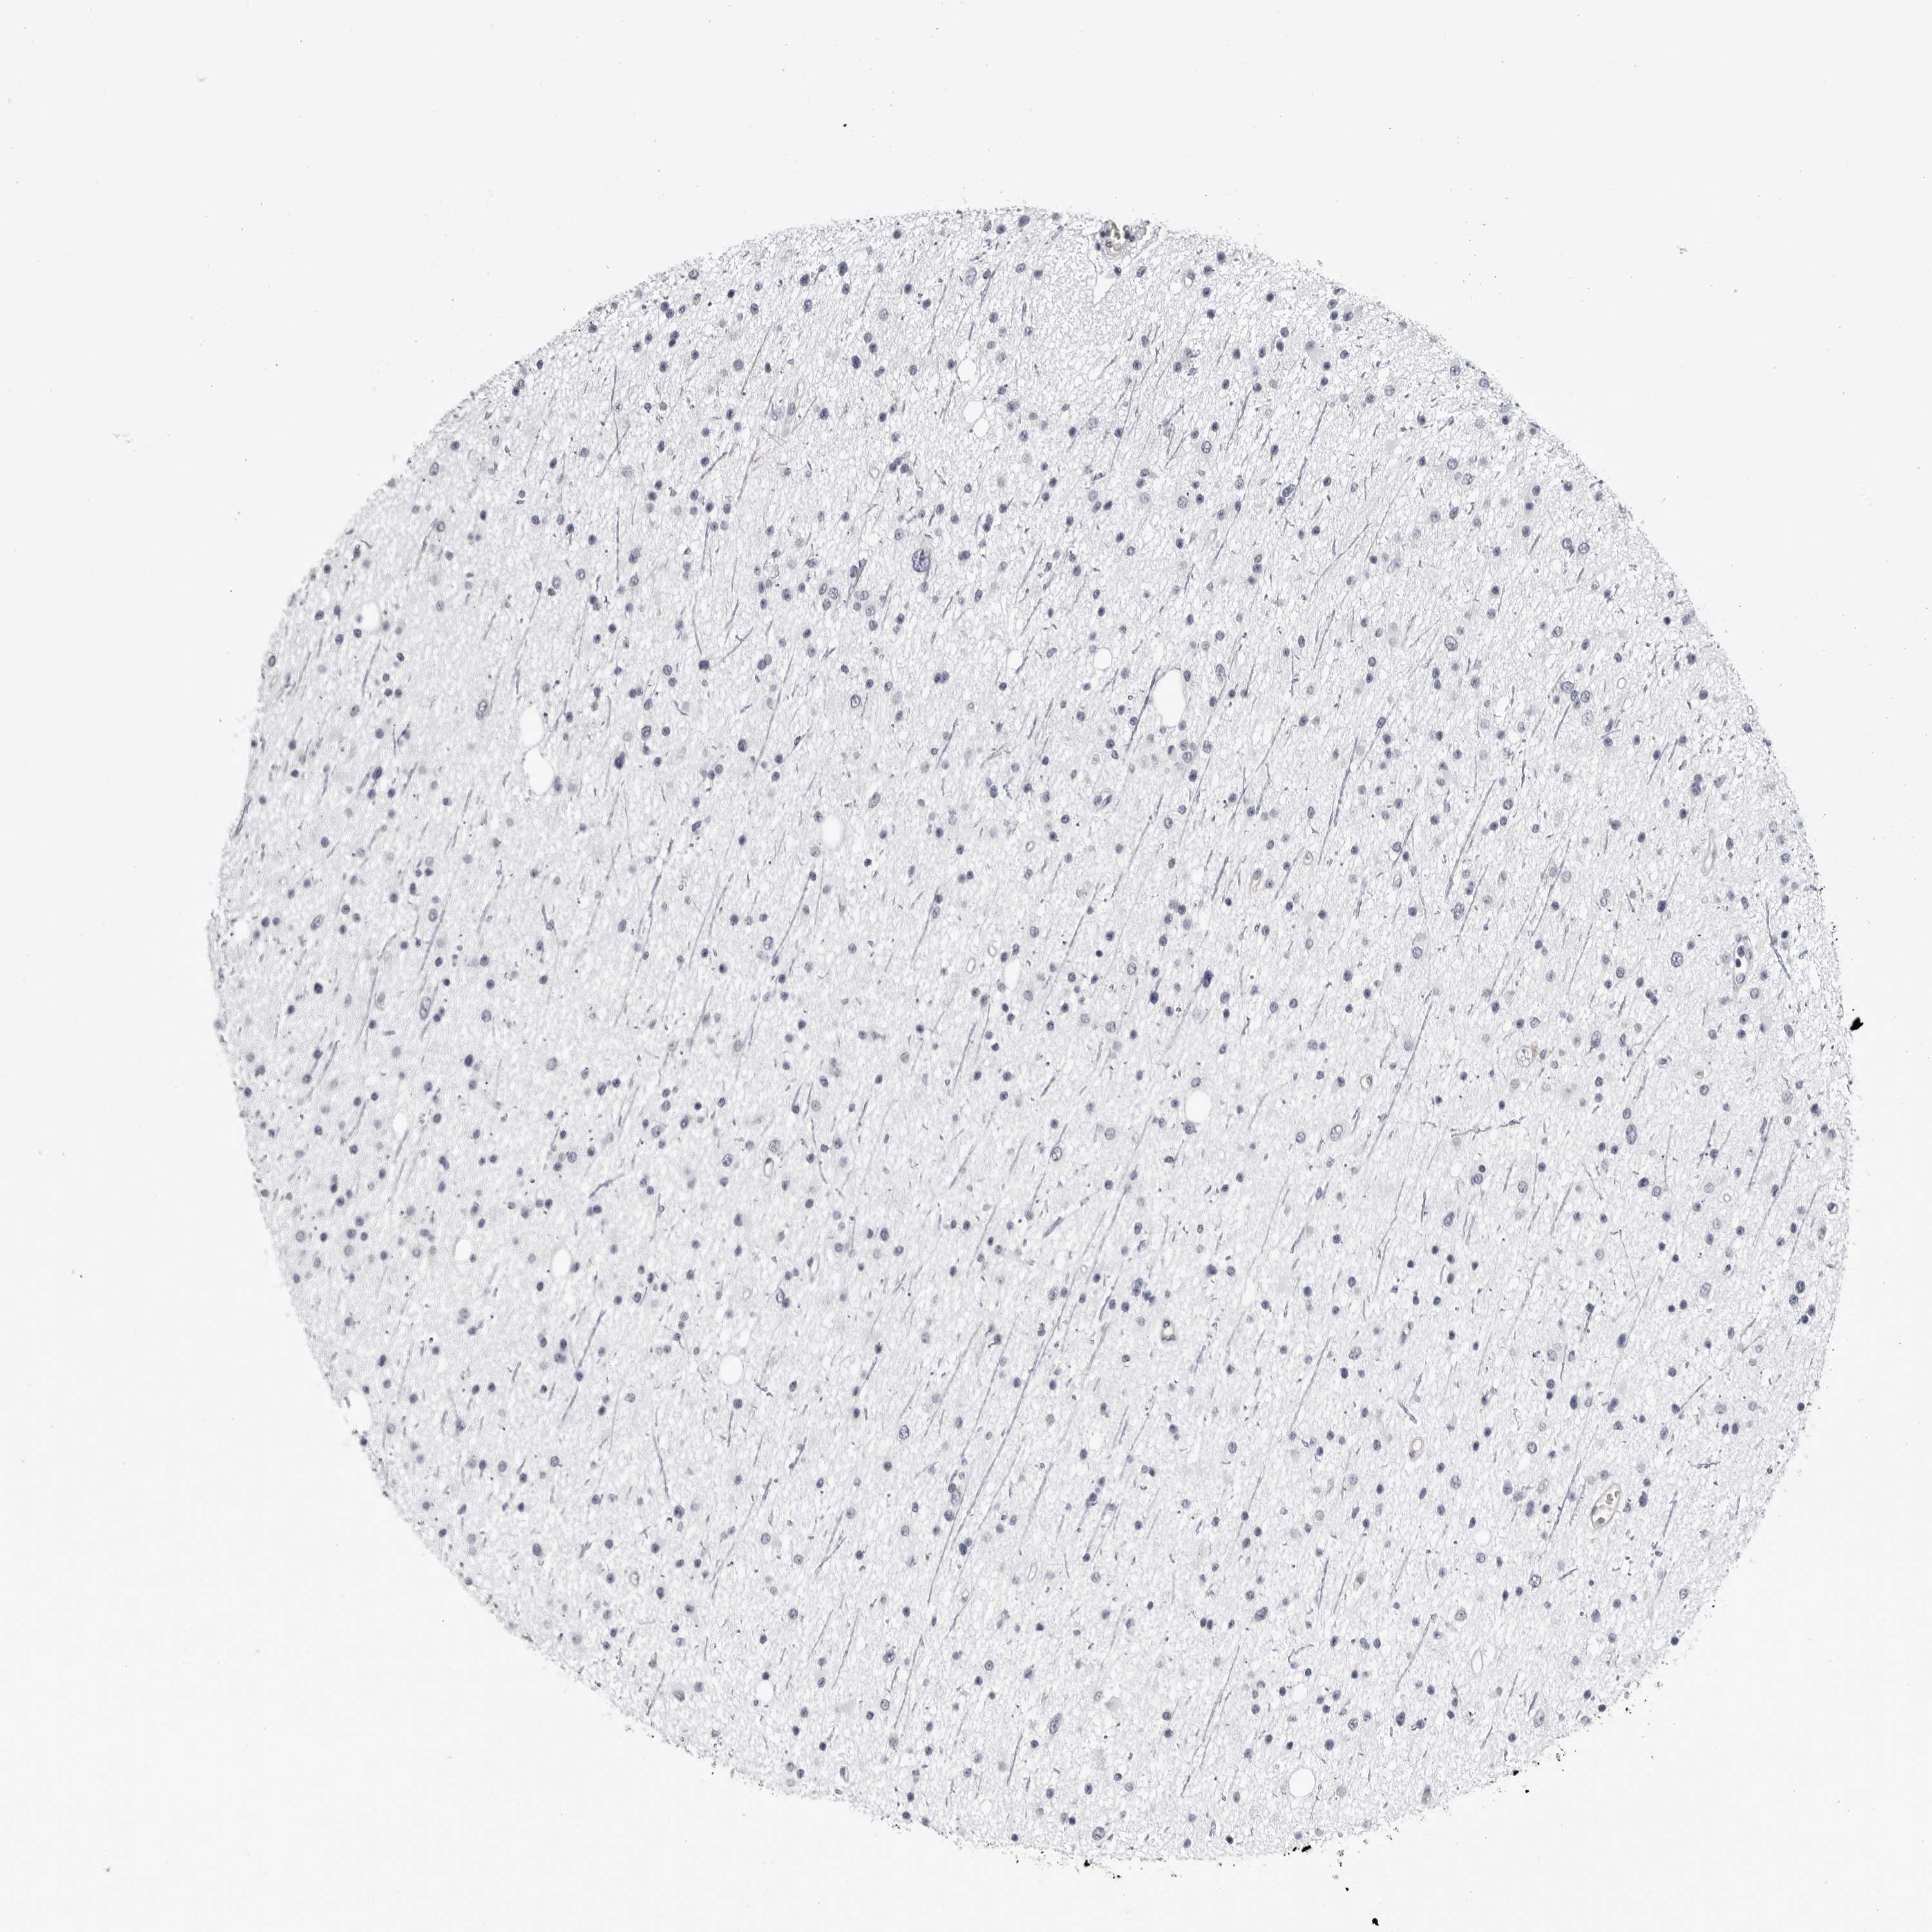

GLIOMA - Protein expressioni

A mouse-over function shows sample information and annotation data. Click on an image to view it in a full screen mode. Samples can be filtered based on level of antibody staining by selecting one or several of the following categories: high, medium, low and not detected. The assay and annotation is described here.

Note that samples used for immunohistochemistry by the Human Protein Atlas do not correspond to samples in the TCGA dataset.

Antibody stainingi

Antibody staining in the annotated cell types in the current human tissue is reported as not detected, low, medium, or high, based on conventional immunohistochemistry profiling in selected tissues. This score is based on the combination of the staining intensity and fraction of stained cells.

Each image is clickable and will lead to virtual microscopy that enables deeper exploration of all samples and also displays staining intensity scores, fraction scores and subcellular localization as well as patient and tissue information for each sample.

Antibody HPA024761

Antibody HPA029557

Staining

High

Medium

Low

Not detected

Intensity

Strong

Moderate

Weak

Negative

Quantity

>75%

75%-25%

<25%

None

Location

Nuclear

Cytoplasmic/membranous

Cytoplasmic/membranous,nuclear

Glioma, malignant, High grade

Glioma, malignant, Low grade